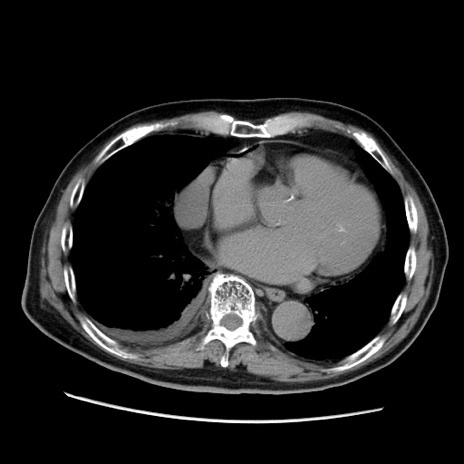

症例21(横断像)

【症例】70歳代男性

【現病歴】肝硬変・肝細胞癌にてかかりつけの方。約9時間前に食後より腹痛出現。症状が徐々に増悪し、嘔吐出現したため来院。

【既往歴】肝硬変、肝細胞癌(RFA、TACE後)